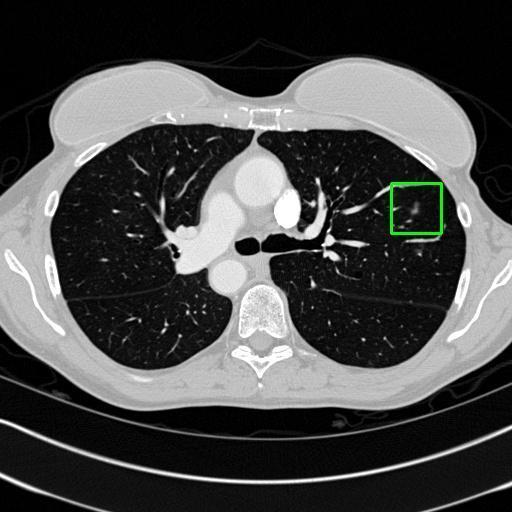

We developed an AI-based system using deep learning models for analyzing lung CT scans to detect and classify pulmonary nodules. We chose the YOLOv11 architecture for its enhanced object detection capability and adapted it specifically for medical imaging, incorporating pixel-level precision and severity classification.

Classification into three severity levels with colored bounding boxes.

Successfully built and deployed an AI model (YOLOv11) capable of detecting lung nodules in CT scans with high accuracy and real-time performance.

Achieved ~0.90 mAP@0.5 on validation data, showing strong object detection capabilities even on complex medical images.

Designed a severity classification system that categorizes nodules into null, moderate, and severe using colored bounding boxes, assisting in rapid clinical decision-making.